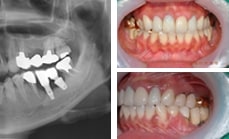

13.07.31 보철제작 후, 약 5년 경과 사진

: 약간의 잇몸뼈 흡수가 관찰되지만,

훌륭한 stability를 유지하고 있다.